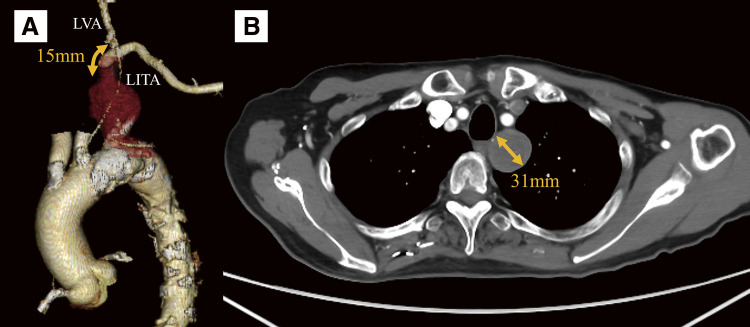

锁骨下动脉瘤是罕见且具有挑战性的治疗,由于其解剖位置和接近关键分支,包括椎动脉。我们报告的情况下,78岁的男子左锁骨下动脉瘤。动脉瘤位于纵隔,直径为31毫米。动脉瘤近端用支架封闭,远端通过锁骨上切口直接结扎。术后影像学证实完全排除。这种混合入路避免了侵入性开放手术,并提供了良好的结果。

Subclavian artery aneurysms are rare and challenging to treat owing to their anatomical location and proximity to critical branches, including the vertebral artery. We report the case of a 78-year-old man with a left subclavian artery aneurysm. The aneurysm was located in the mediastinum and measured 31 mm in diameter. The proximal side of the aneurysm was sealed with a stent graft, while the distal side was accessed through a supraclavicular incision and directly ligated. Postoperative imaging confirmed complete exclusion. This hybrid approach avoided invasive open surgery and provided a favorable outcome.